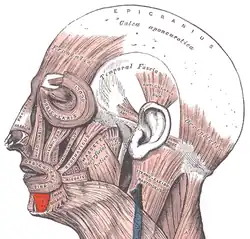

Mięsień obniżacz wargi dolnej (łac. musculus depressor labii inferioris, musculus quadratus labii inferioris) – w anatomii człowieka czworokątny, płaski mięsień wyrazowy, należący do grupy mięśni otoczenia szpary ust[1]. W powierzchownej części jest przedłużeniem mięśnia szerokiego szyi, a reszta włókien zaczyna się na dolnym brzegu żuchwy nad przyczepem mięśnia obniżacza kąta ust. Kończy się w skórze wargi dolnej[1]. Unerwiony jest przez gałąź brzeżną żuchwy nerwu twarzowego[1].

Obniża, uwypukla i pogrubia wargę dolną[1].